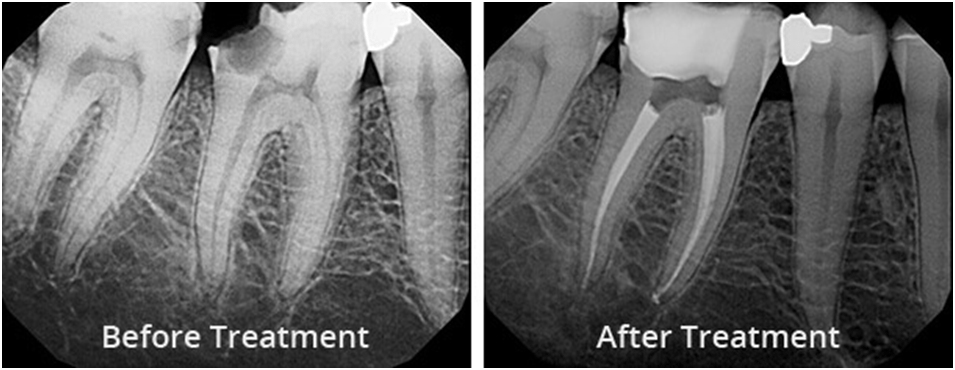

• Filling the Canal

Filled with Gutta Percha, a thermoplastic material, and sealed with a biocompatible sealer.

• Permanent Filling & Crown

To restore strength and function, a crown is placed after filling.

Is Root Canal Treatment Successful?

Yes! RCT is a highly successful and widely performed procedure. It involves removing the infection from within the tooth and protecting it from future bacterial invasion. With proper care and restoration (like crown placement), your treated tooth can last for many years—even a lifetime!